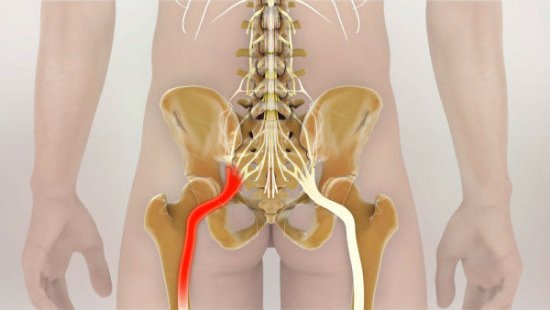

- Если болят мышцы на спине вдоль позвоночника, то это говорит о развитии грыжи и сколиоза. Болевые ощущения возникают из-за того нервные корешки сдавливаются, и части позвоночника меняют свое привычное положение.

- Появление поясничного остеохондроза характеризуется образованием боли в области поясничного отдела. Она внезапная с прострелами. Болят мышцы в области поясницы и ног. При этом отдает в пах и таз. Если позвонки срастаются, то она может стать меньше или вообще пропасть. При этом у пациента появляется чувство онемения кожи, парез и паралич верхних конечностей. У мужчин появляются проблемы с посещением туалета. У женщин — нарушается менструальный цикл.

Еще один источник болей в пояснице – наличие межпозвонковых грыж. При их ущемлении, сдавливании нервных корешков возникает довольно сильная, резкая боль, справиться с которой на начальных стадиях помогают стероидные и нестероидные противовоспалительные препараты.

Грыжа позвоночника – частая причина боли

Признаком неблагоприятного исхода является люмбалгия, которая проявляется спектром разнообразных симптомов. Боли по ходу нервного корешка могут отдавать в ягодицы и ступни. Дискомфорт появляется при наклонах (даже при наклоне головы вниз), смехе, кашле и т. д. Болевой синдром усиливается при поднятии лежа на спине прямой ноги.